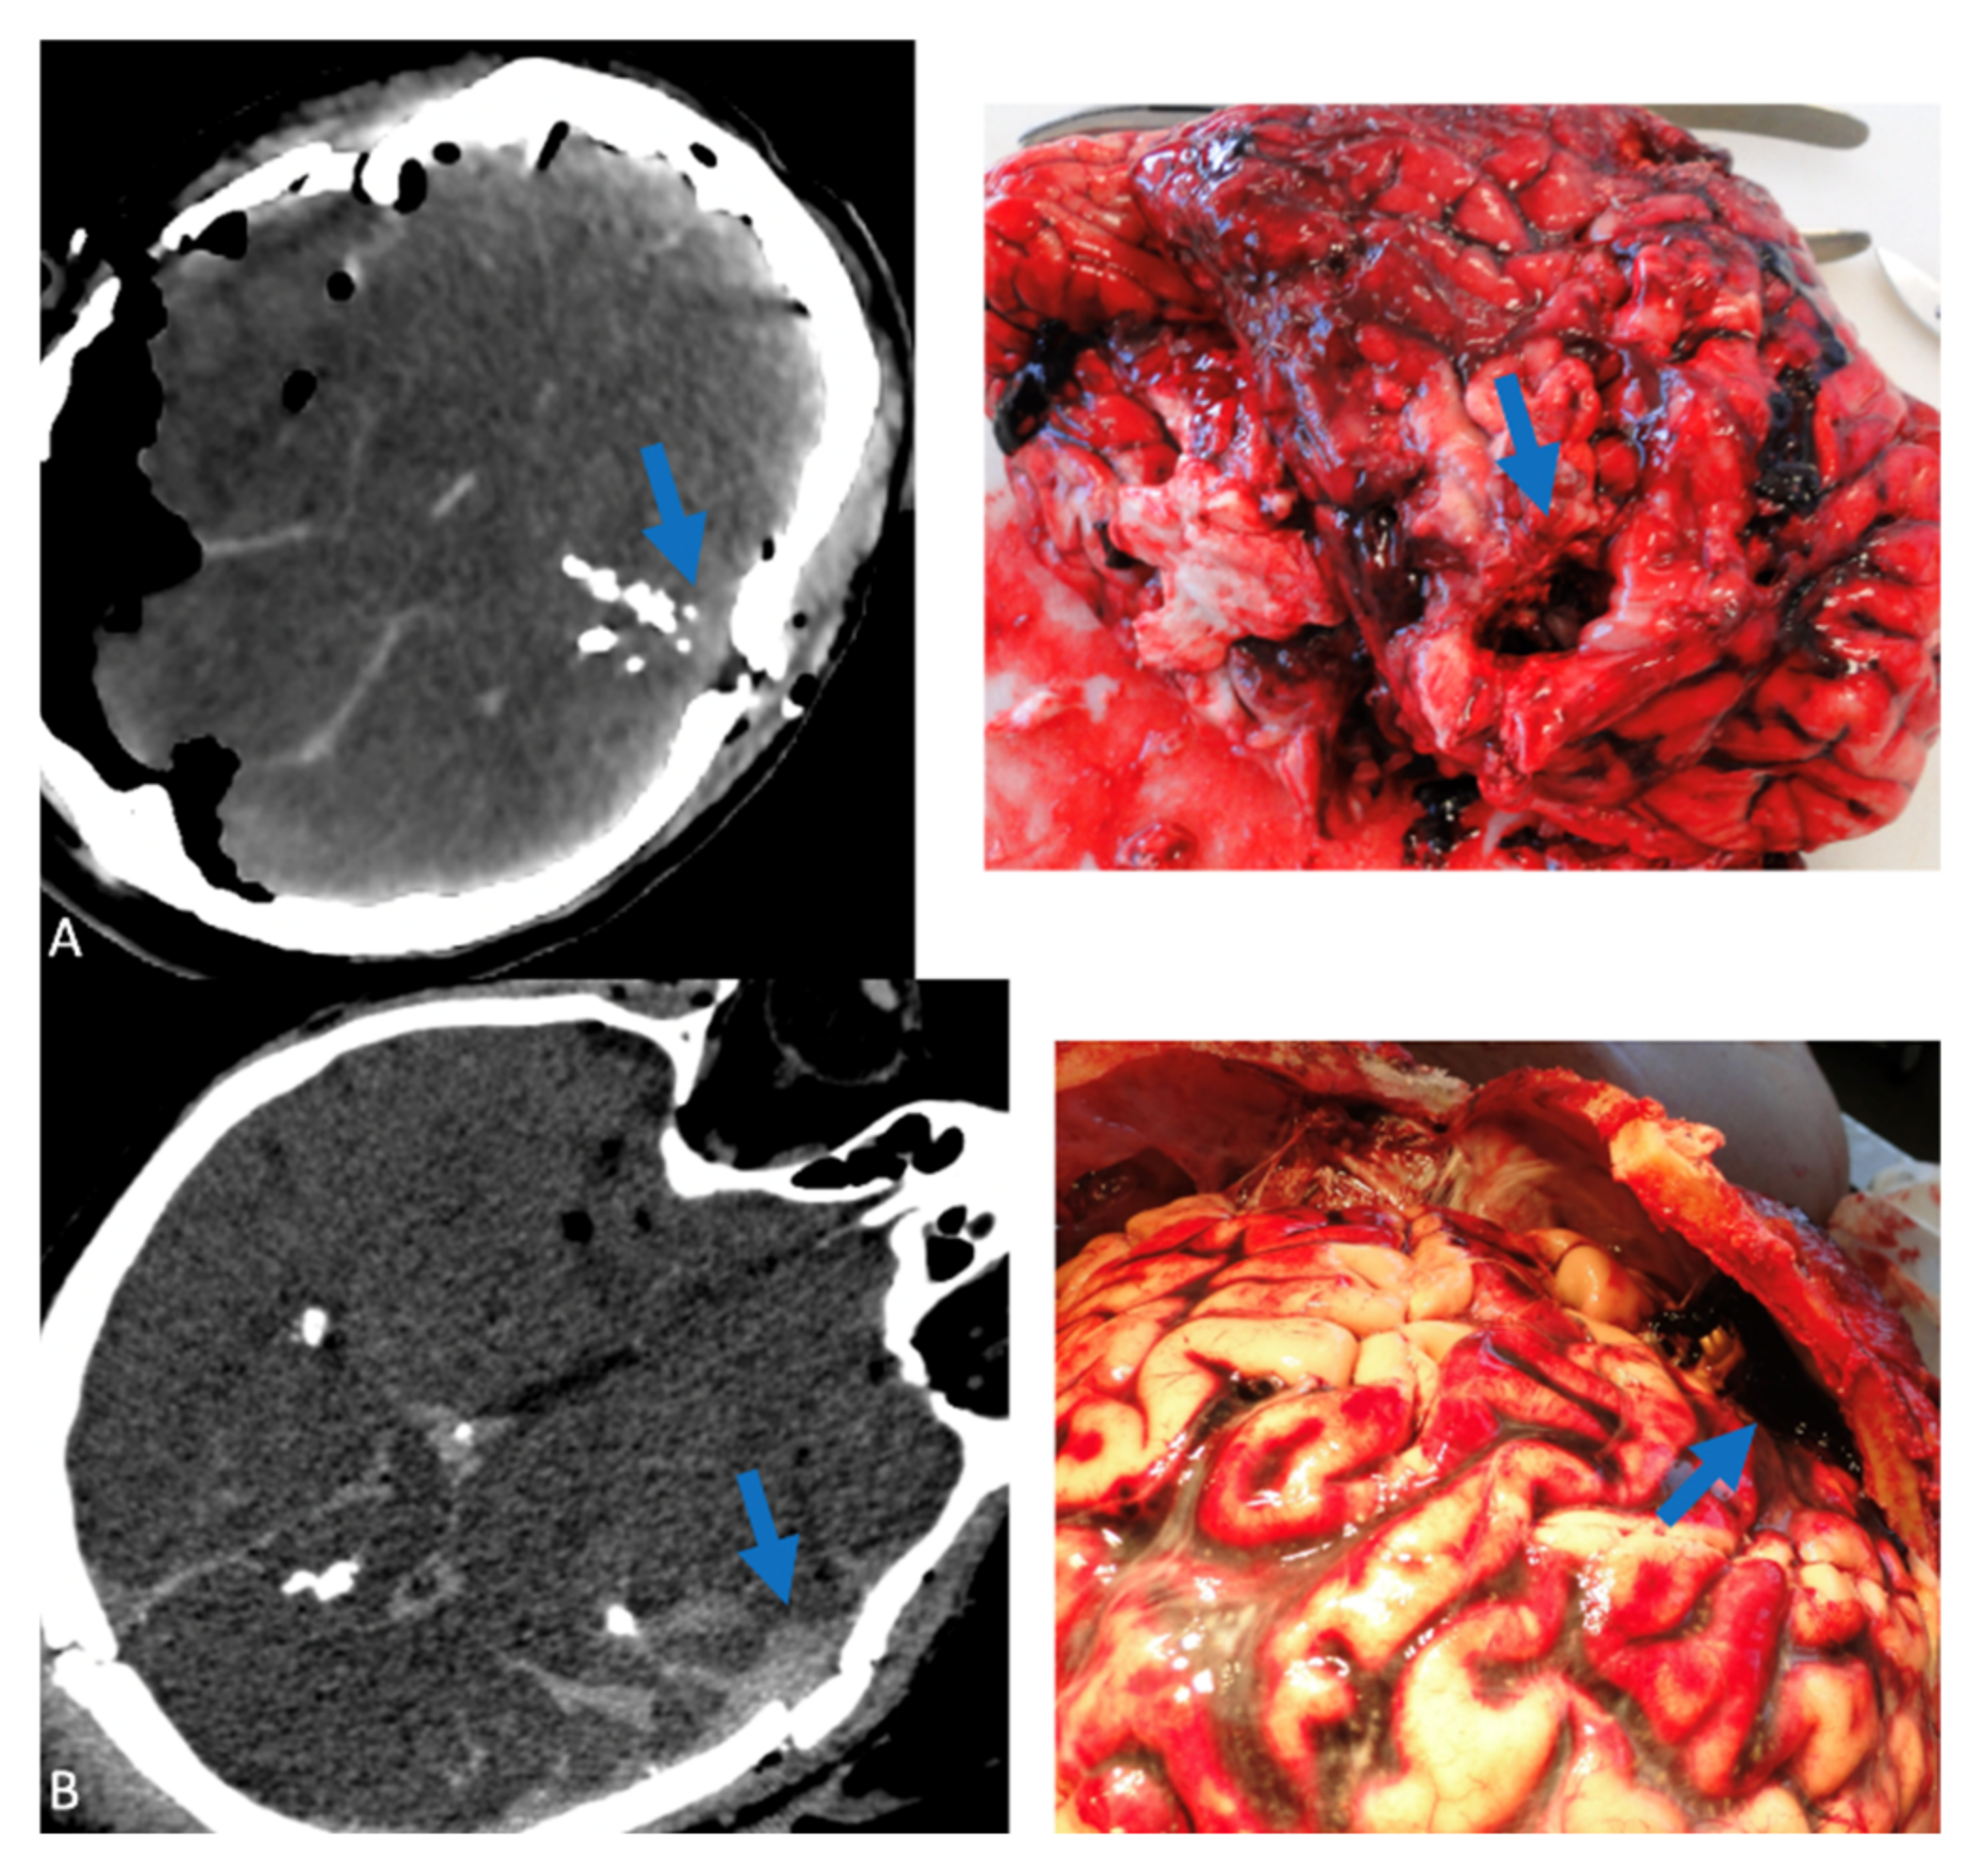

Figure 1, Figure 2 and Figure 3 show correlations between CT scan data and autopsy photographs.

Figure 2. Correlations between CT scan and autopsy concerning thoracic lesions (arrows) (A) heart lesion, (B) right lung lesion, (C) lesion of the posterior wall of the trachea.